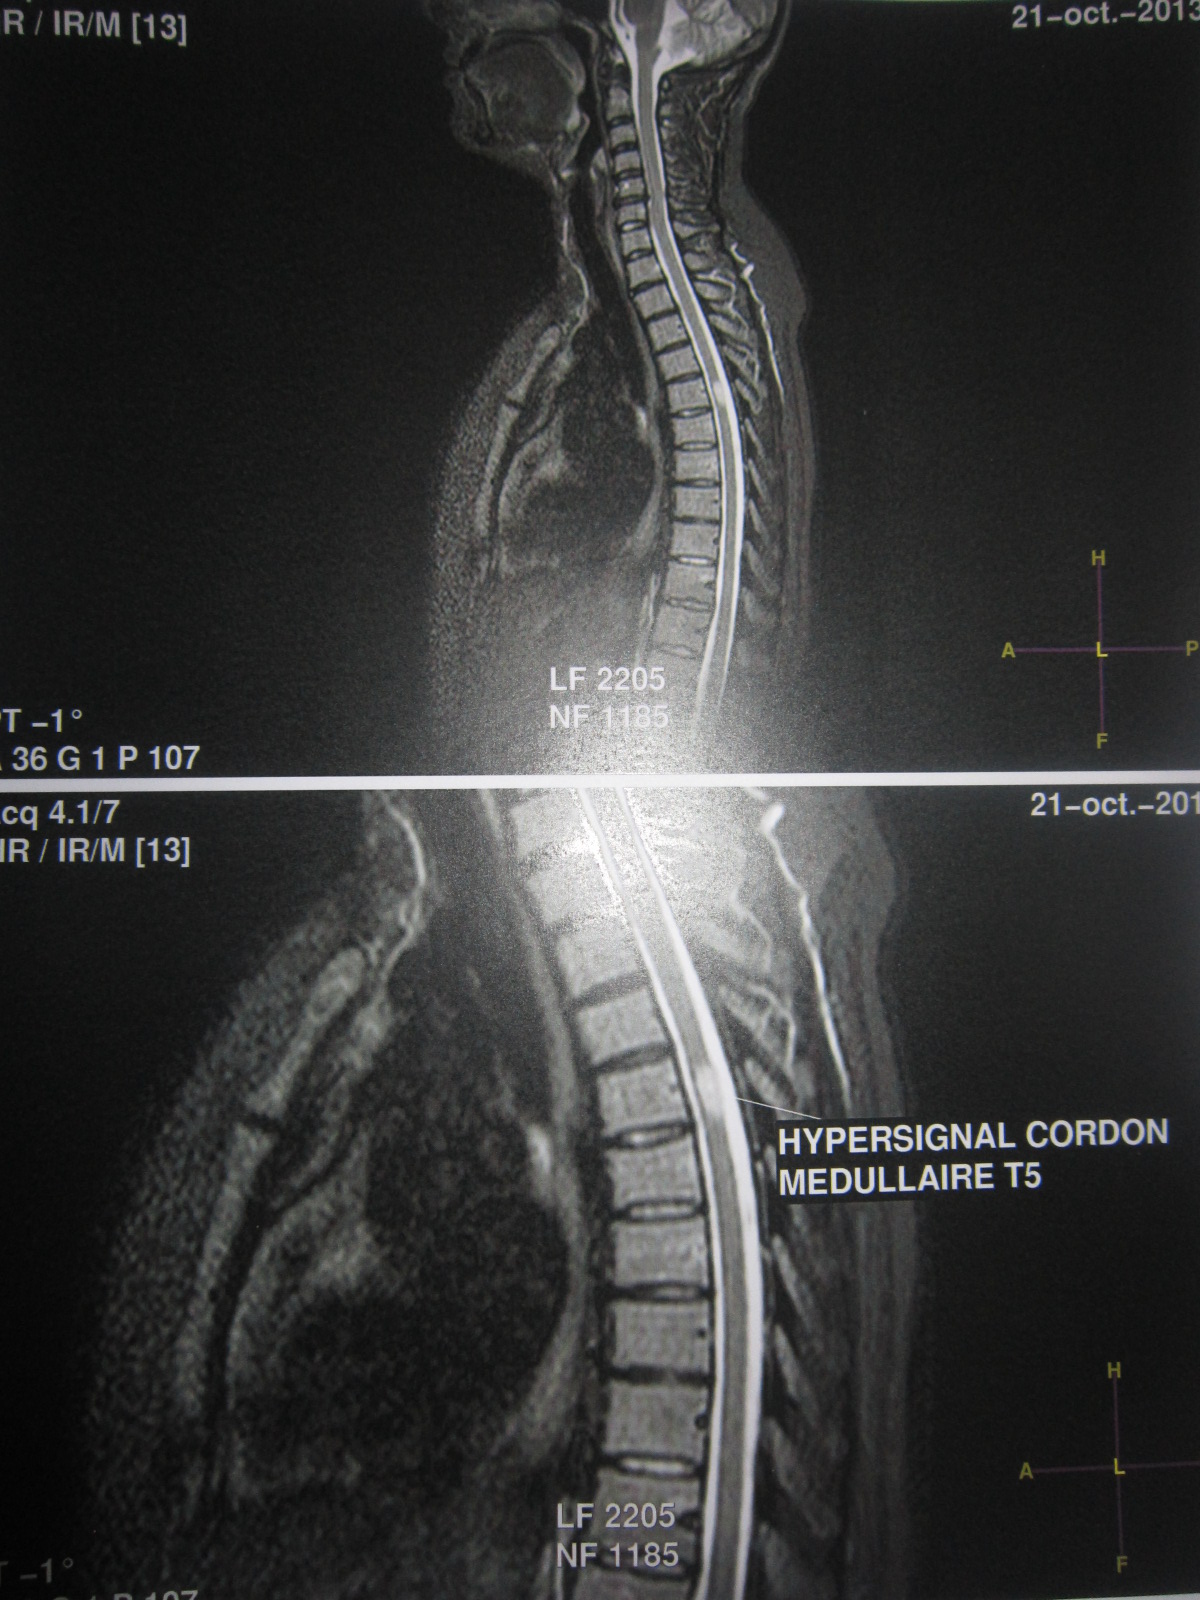

Sep Et Deni De La Maladie Besoin D En Parler Sclerose En Plaques Forum Sante Doctissimo